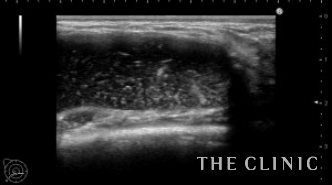

術前のエコーです。通常ヒアルロン酸はエコーでは黒く描出されますが、炎症により白い部分が多くなっています。